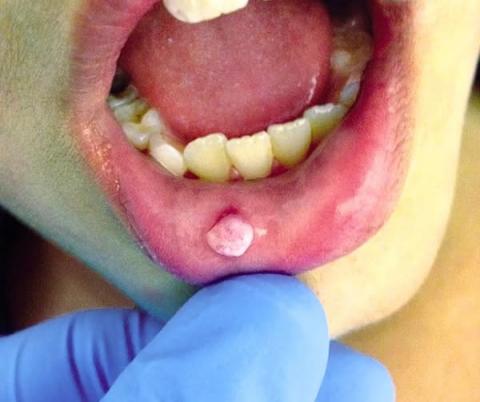

Oral Papilloma: Symptoms and Treatment in the Philippines | Tony's Story

More Than Just a Festive Ouch: When a Bitten Tongue in Manila Leads to a Dental Discovery